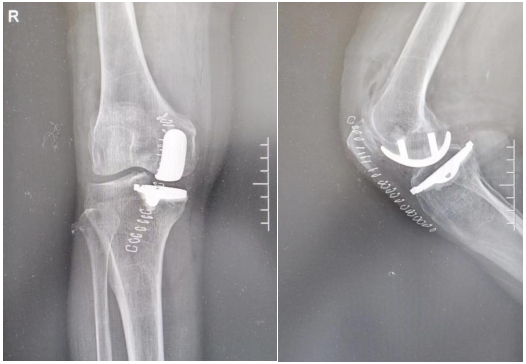

術(shù)后患者的膝關(guān)節(jié)X線片